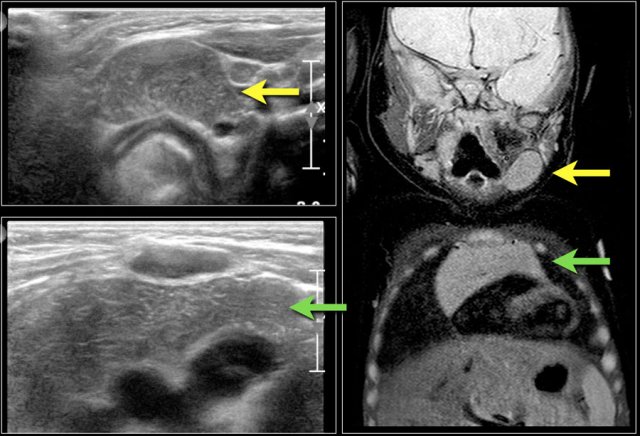

Here images of a six-month old boy with a vocal cord paralysis.

The MRI examination shows a mass between the parotid and submandibular gland (yellow arrow).

The signal characteristics are equal to the thymus (green arrow).

Ultrasound confirmed an ectopic thymic remnant (yellow arrow), with identical sonographic characteristics as the orthotopic thymus (green arrow).

Left: orthotopic thymus; right: ectopic thymus